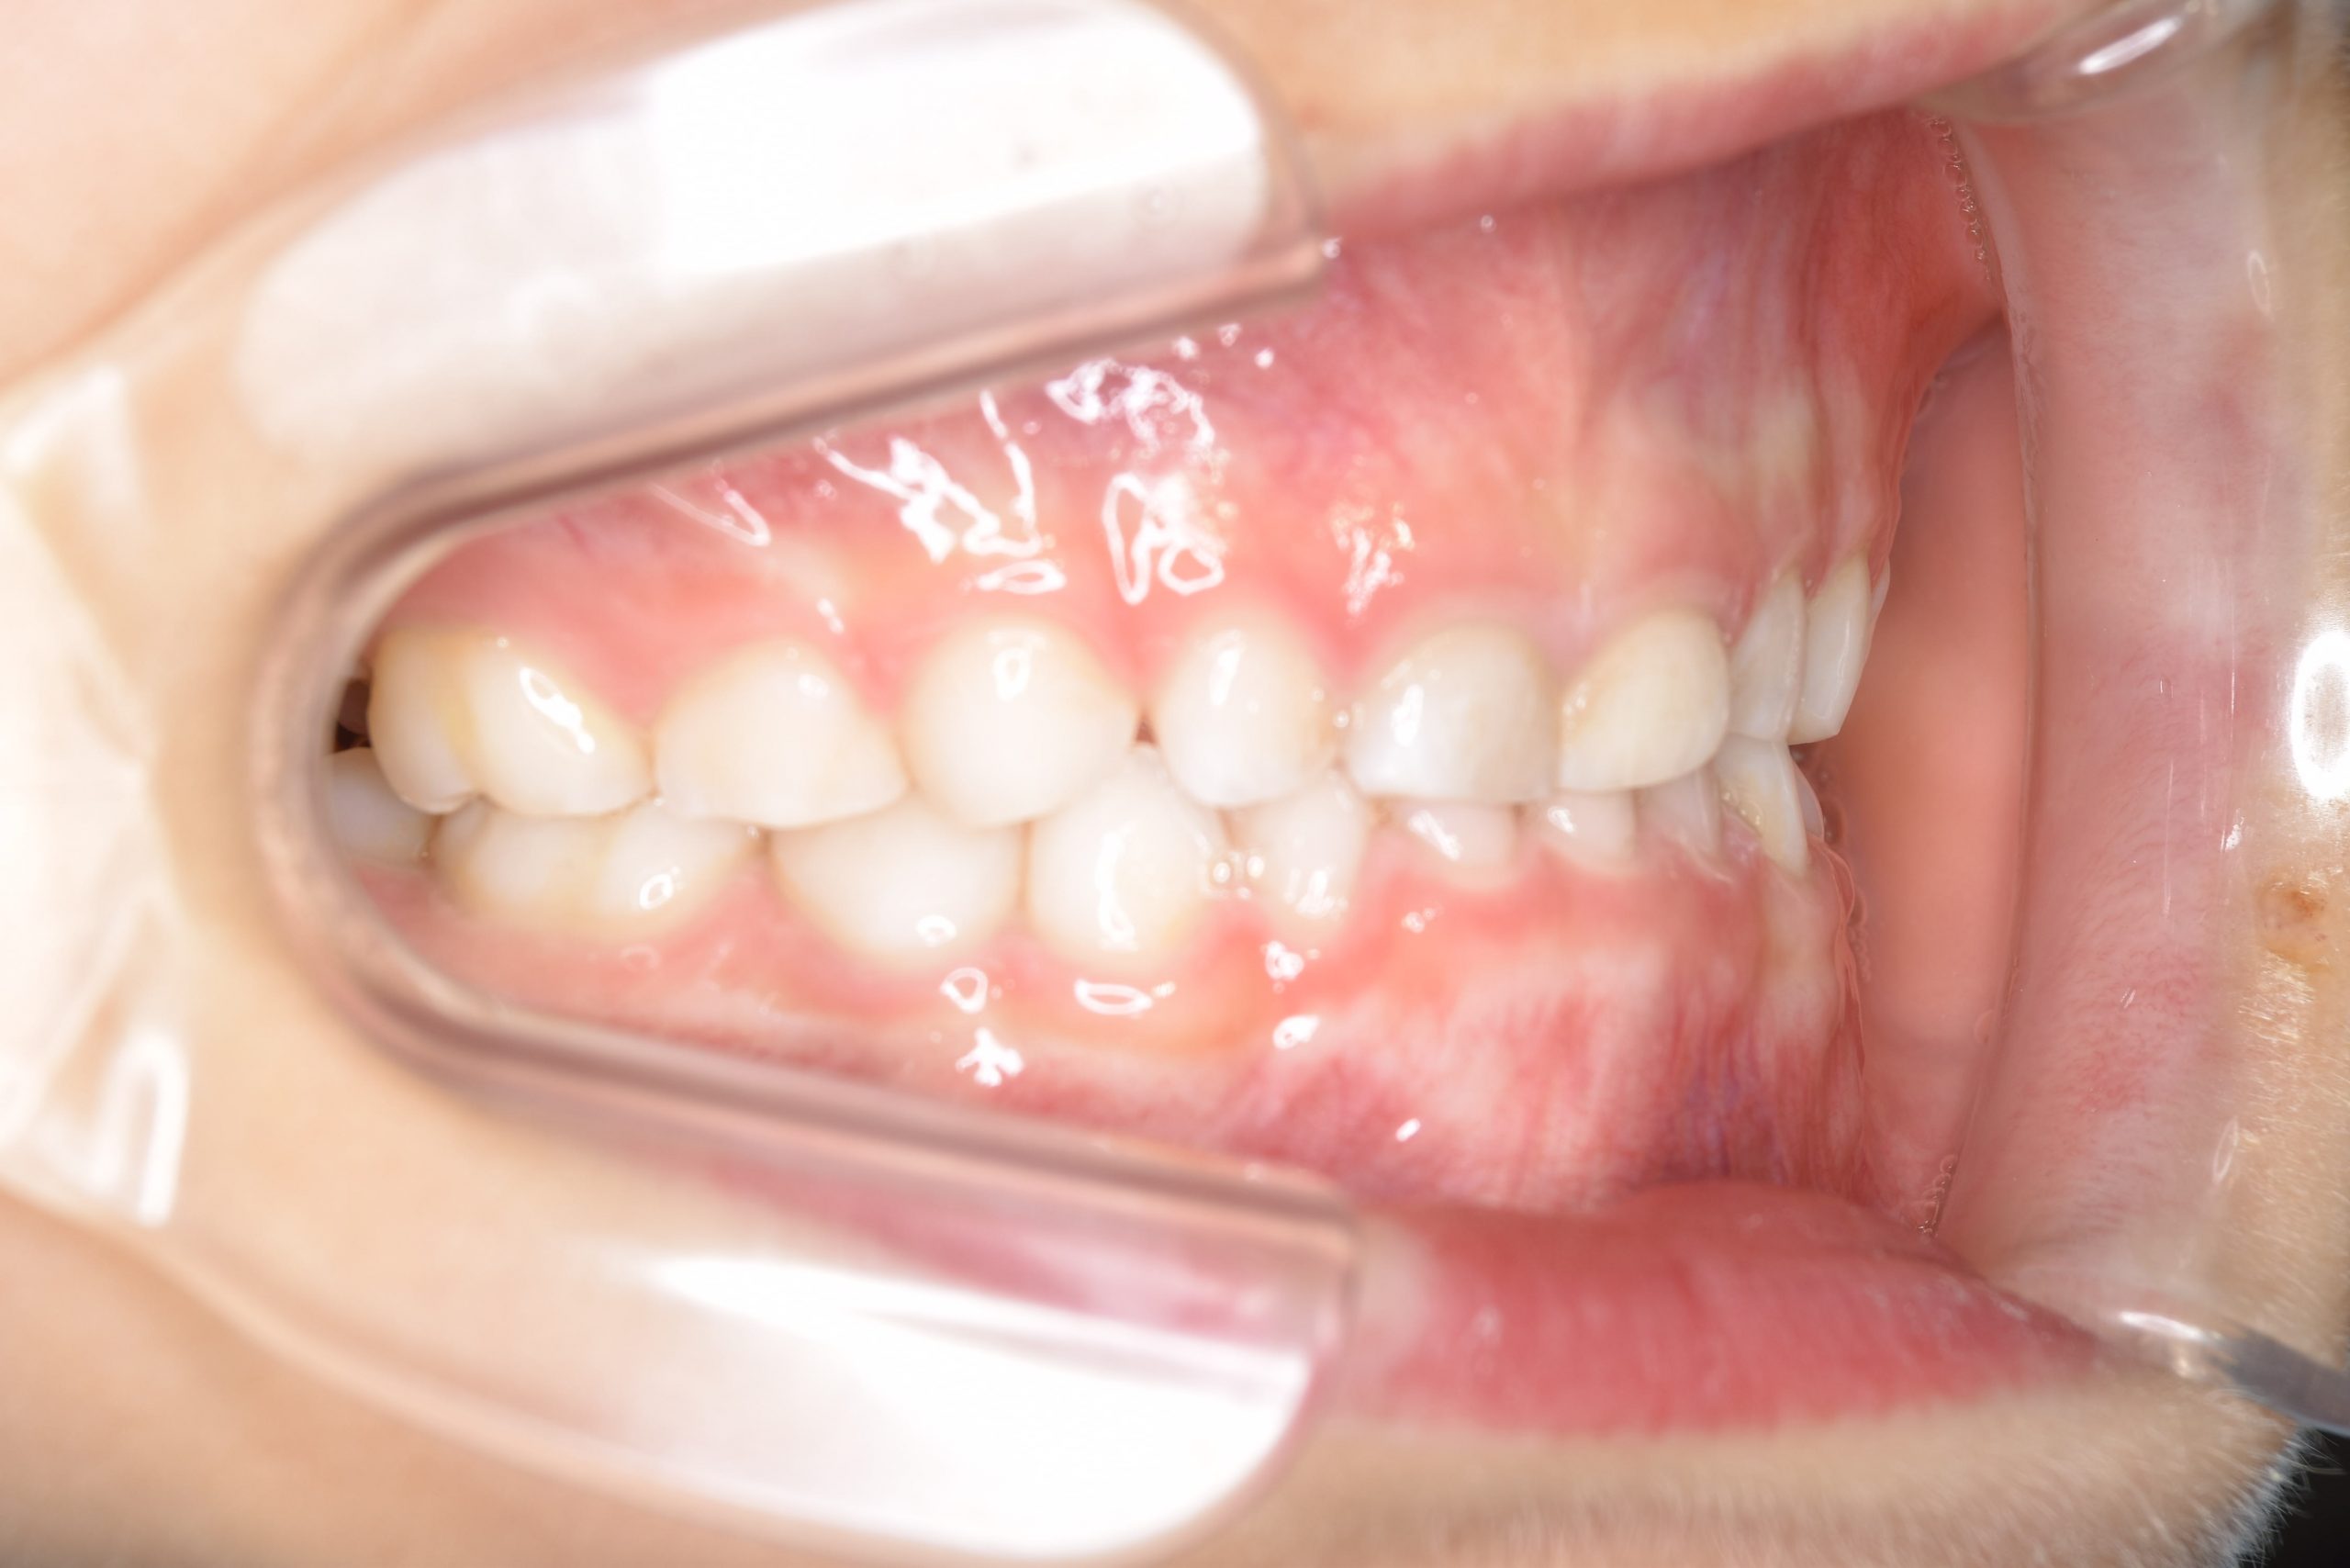

アフター

子どもの矯正治療|症例_121

施術内容 上顎急速拡大装置と下顎リンガルアーチを用いて上下顎骨を拡大した。

その後マウスピース型矯正装置で歯牙を配列し良好な咬合を獲得した。

治癒期間 3年11ヶ月間